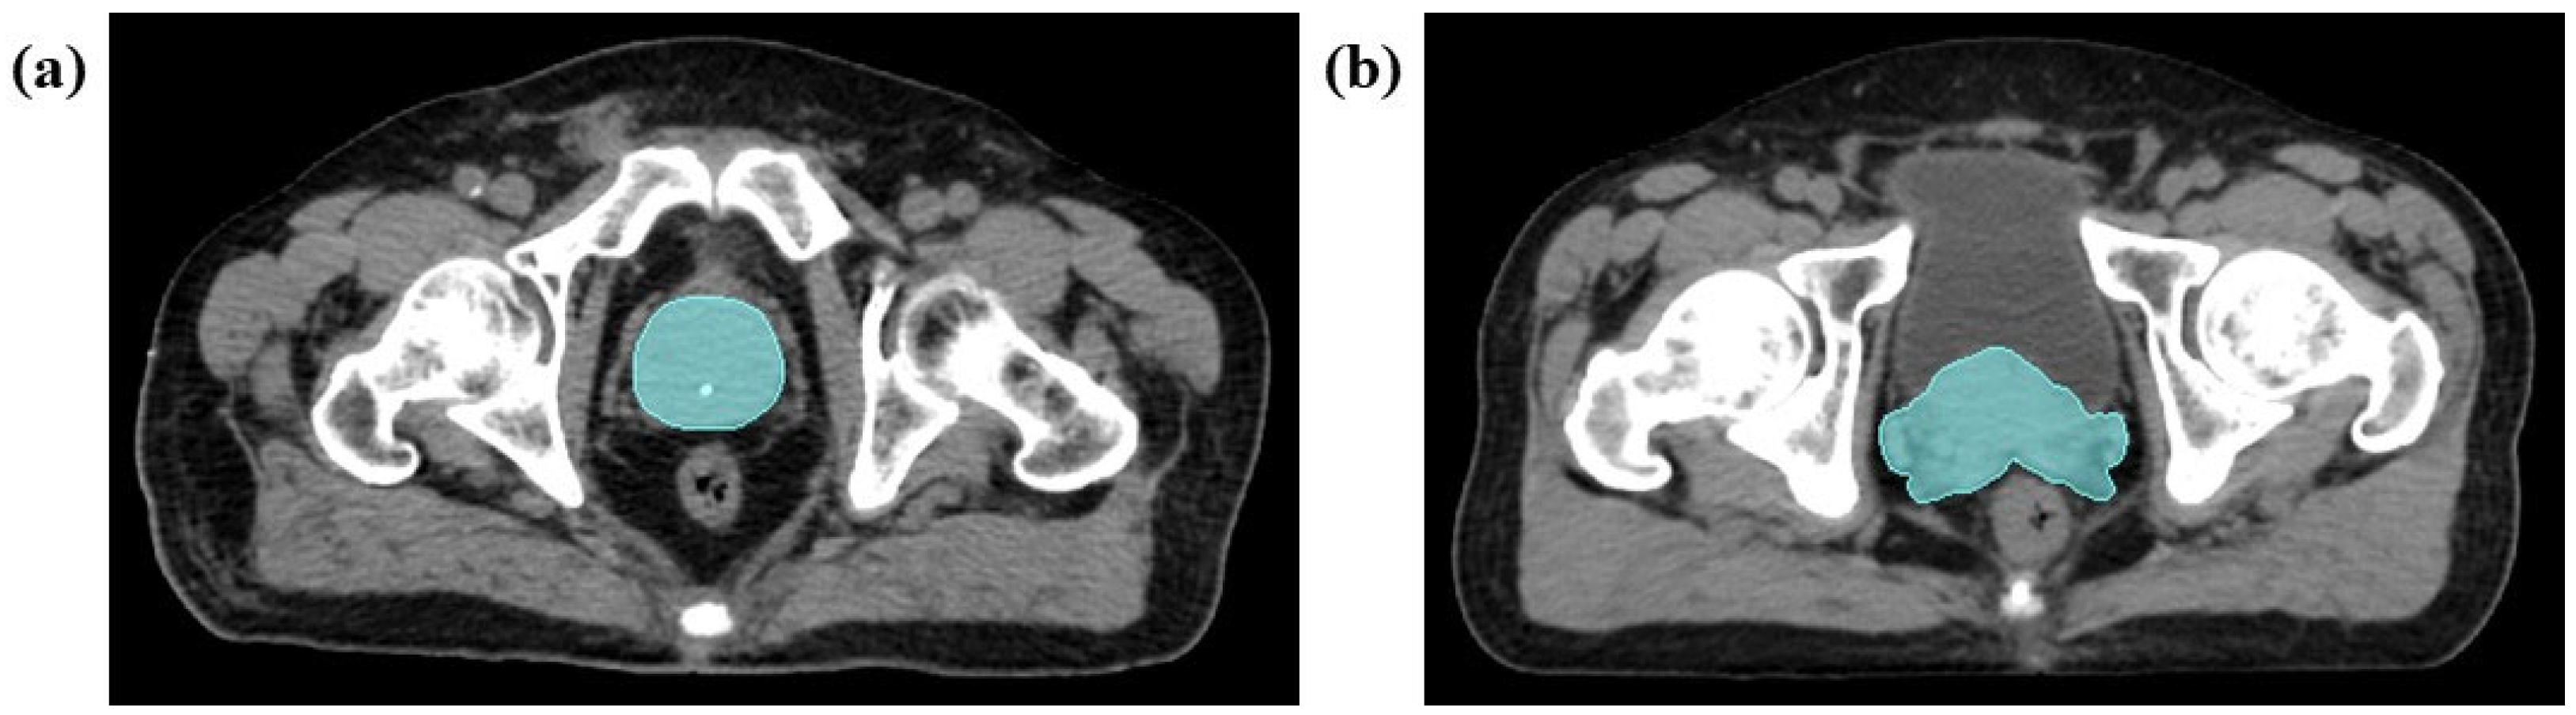

2.4.2. Medical Image Segmentation

2.4.3. Feature Extraction